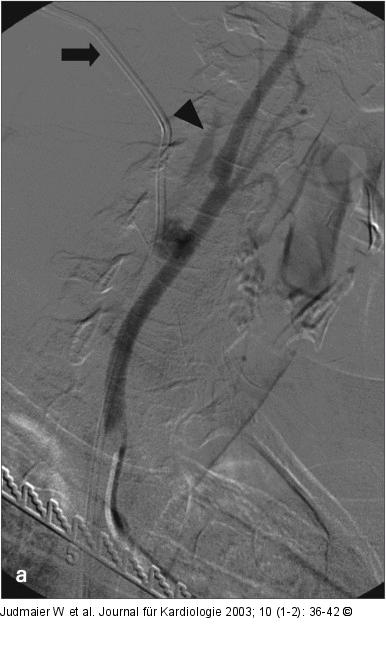

Abbildung 22-b: Arteria carotis communis

Diagnostische Angiographie der rechten Arteria carotis communis mit einem 4 French-Sidewinder-II-Katheter: a) Darstellung eines etwa 20 mm im Durchmesser haltenden Aneurysma spurium der Arteria carotis communis 2 cm proximal der Karotisbifurkation. Weiters dargestellt sind der Schatten des zentralvenösen Katheters (Pfeil) sowie eine flaue Kontrastierung der Vena jugularis interna (Pfeilspitze) über eine AV-Fistel. b) Vergrößerung und Vermessung des Gefäßdurchmessers zur Auswahl eines passenden Stentgrafts nach Applikation von 0,1 ml Perlinganit: Die Arteria carotis communis mißt etwa 6,5 mm. |